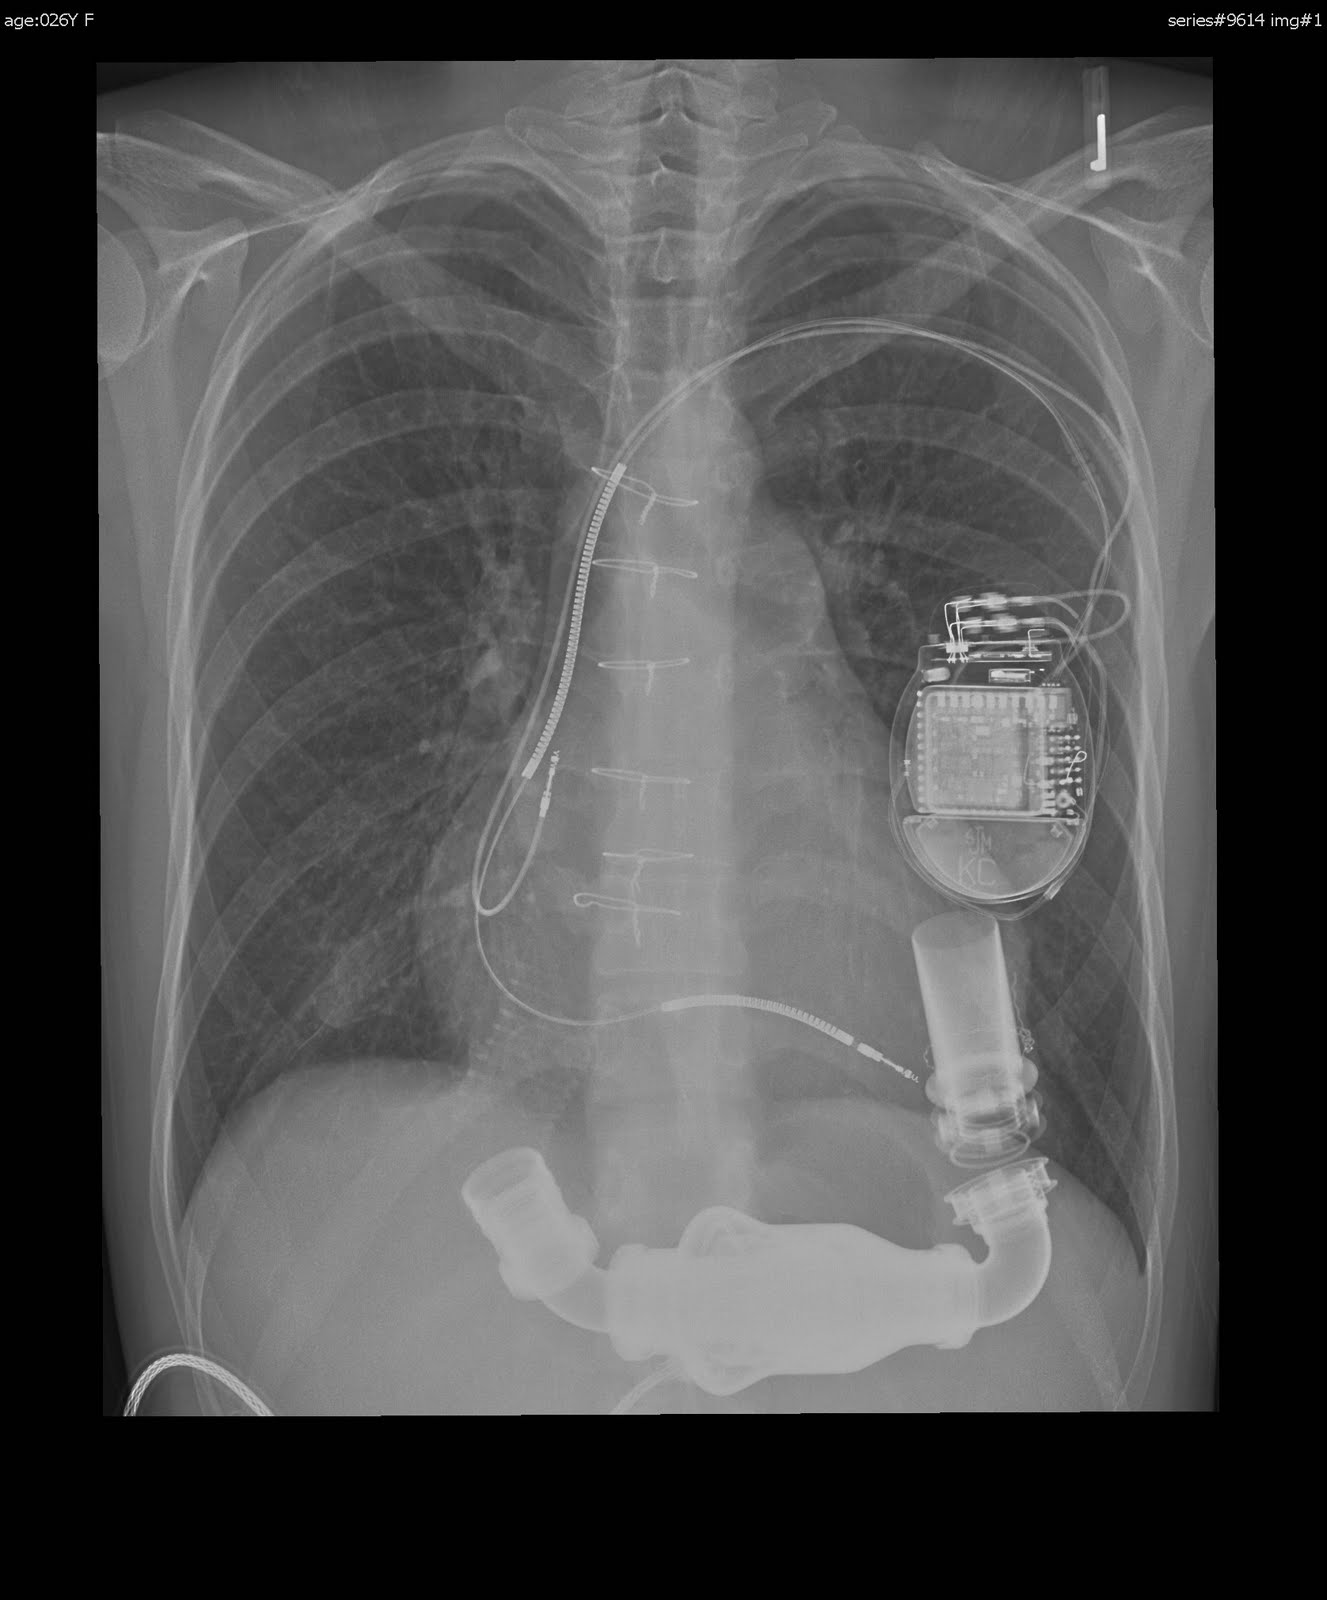

LVAD DRIVELINE